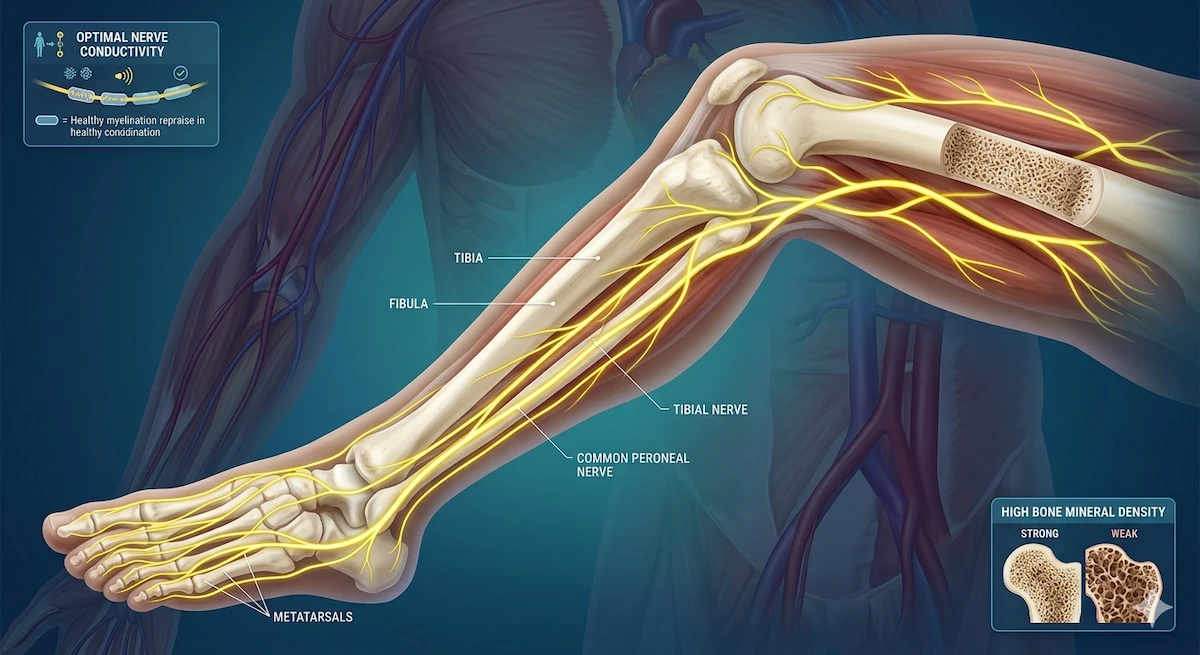

Our body’s joints function in exactly the same way [2]. Bones, joints, and nerves are distinct structures, but they are deeply interconnected; the health of one directly impacts the functionality of the others [2]. When internal inflammation and dryness increase in the body—a condition referred to as excess Vata in Ayurveda—and blood circulation slows down, disaster strikes [2]. The protective cartilage begins to dry up, the essential lubricating fluid decreases, and our nerves become highly sensitive [2].

Despite their tiny size, sesame seeds hide massive bone-building strength [4]. They are packed to the brim with calcium, magnesium, and healthy natural fats [4]. According to Ayurvedic principles, sesame seeds directly nourish the Asthi Dhatu (bone tissue) [4]. Bones don’t just weaken from a lack of calcium; they deteriorate when the body experiences excess dryness, elevated Vata, poor circulation, and a lack of lubrication [4].

The natural oils found in sesame seeds slowly eradicate this internal dryness [4, 7]. If your knees make a “clicking” or “popping” sound, or if you suffer from lower back pain, heaviness, and pain while walking, sesame seeds can provide immense relief [7].

Garlic naturally thins the blood and makes it flow smoother, ensuring that it can easily navigate through the tiny, intricate vessels of your joints and nerves [8]. It contains natural sulfur compounds that relax your blood vessels, vastly improving overall circulation [8]. This means your cartilage undergoes less wear-and-tear, and your nerves receive the optimal oxygen and nourishment they desperately need [9]. For those experiencing tingling, numbness, or rapid fatigue in their legs and hands, garlic is incredibly beneficial [8, 9].